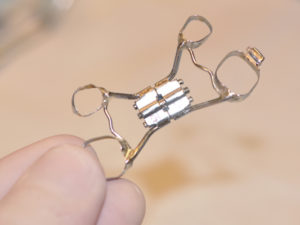

- Συσκευή Quad Helix

- Συσκευή Quad Helix

- Συσκευή Quad Helix